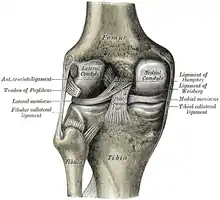

Head of right tibia seen from above, showing menisci and attachments of ligaments.

Head of right tibia seen from above, showing menisci and attachments of ligaments. Capsule of right knee-joint (distended). Posterior aspect.

Anterior view of knee. Knee joint. Deep dissection. Anterior view

Knee joint. Deep dissection. Anterior view